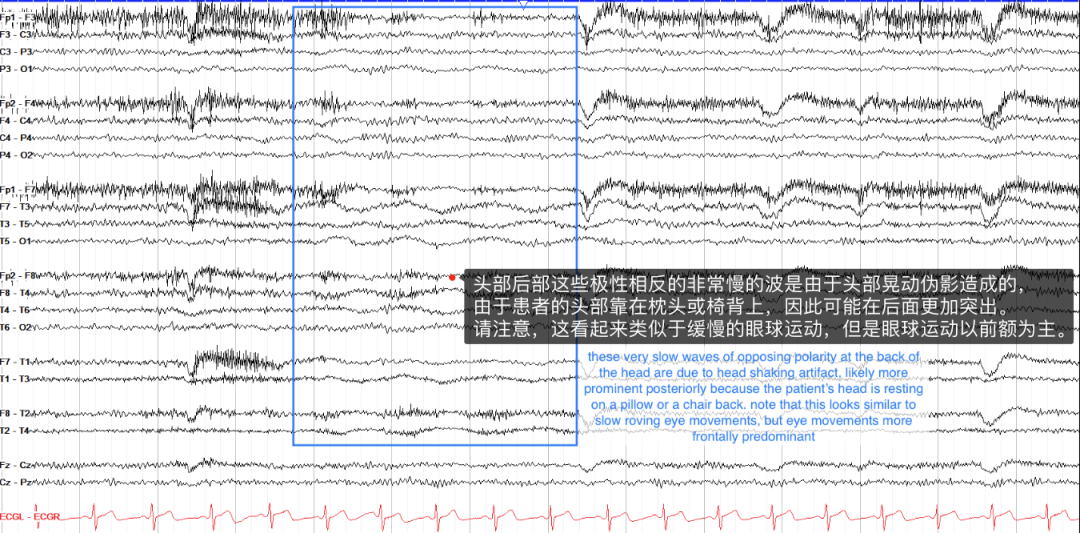

其中,摇头伪影可能稍微棘手一些,其特点是缓慢、低幅度的活动,如果患者将头枕在枕头上,这种活动通常在后方更为明显。它看起来类似于困倦时的眼球游动,但眼球运动是在前导联中。